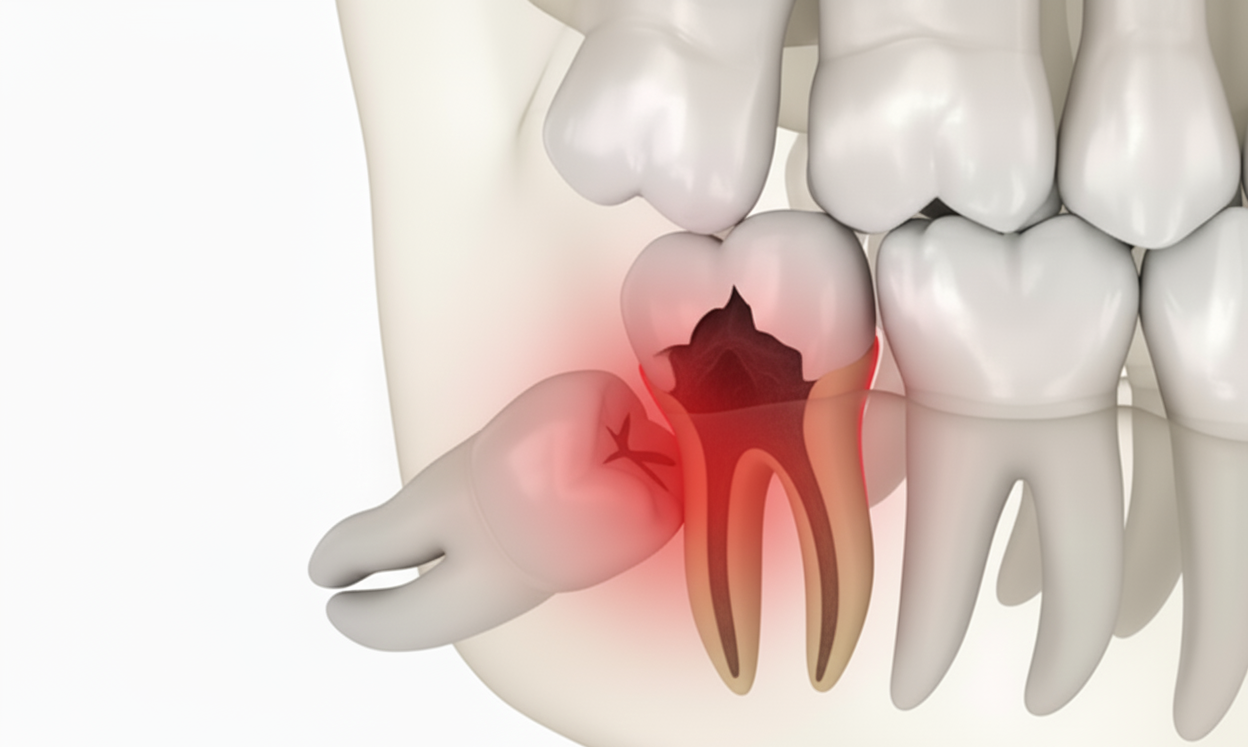

Impaction - Minor-Surgery In Chennai

Impaction in dentistry refers to a condition where a tooth is unable to fully emerge (erupt) through the gum line into its normal position in the mouth. This usually happens because there isn’t enough space in the jaw or because the tooth is coming in at an incorrect angle. The most commonly impacted teeth are the third molars, also known as wisdom teeth.

At Best Dental Clinic – Dr N Deenadayalan T Nagar, Chennai and Dr Julian’s Laser Dental Clinic Tambaram, Chennai., our expert dentists provide professional impaction minor surgery in Chennai, including management of impacted wisdom teeth.

Causes of Impaction:

-

Lack of space in the jaw

-

Overcrowding of teeth

-

Abnormal tooth angulation

-

Thick or overlying gum tissue or bone

Treatment:

Impacted teeth, especially impacted wisdom teeth in Chennai, are often surgically removed at Best Dental Clinic – Dr N Deenadayalan T Nagar, Chennai and Dr Julian’s Laser Dental Clinic Tambaram, Chennai. to prevent or resolve complications.